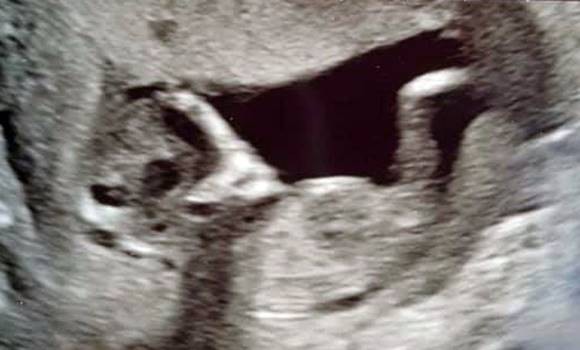

Their excitement turned to shock when they saw the ultrasound images from one examination. At first they thought the doctor might have forgotten to tell them they were expecting twins. On the ultrasound, next to their daughter, they saw a strange figure:

• It was hovering above the baby’s figure.

• Its face resembled the most famous depiction of an alien.

If you picture a small innocent baby and next to it a creepy figure of something with a face that looks like an alien, it will frighten you a bit.

Shocked, Sophie describes her ultrasound image as follows: „We saw that extra eyes were appearing above our child’s figure. Also, the head belonging to those eyes resembled an alien – it was like something out of a movie. I was afraid that the alien would attack and eat my child.“ However, with her own brand of humor she adds: „I used to date a guy who believed in aliens and demons, so we fear he must have cast a curse on me.“